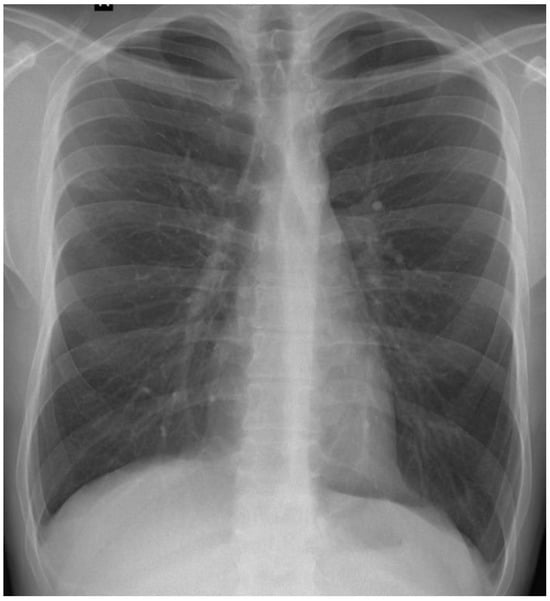

A posteroanterior chest radiography (chest X-ray) before admission revealed a high-intensity opacity with indistinct margins and a heterogeneous appearance, localized in the right suprahilar region (Figure 1). Subsequent native and contrast-enhanced chest computed tomography scans (CT) identified centrilobular micronodules and consolidations associated with linear lesions that showed a characteristic “tree-in-bud” pattern in the right upper lobe, along with fluid accumulation in the right pleural cavity, suggestive of secondary pulmonary TB or other infectious ethiology (Figure 2).

Figure 1. Chest X-ray showing high-intensity opacity in right suprahilar region (red arrow).